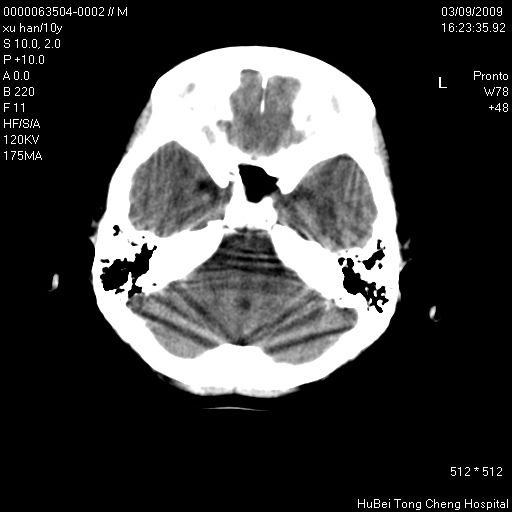

以下是引用道哥在2009-3-9 18:40:00的发言:[br]未见明显异常,必要时mr(dwi)成像。

以下是引用余辉在2009-3-10 11:01:00的发言:[br]考虑双侧海马急性缺氧性损伤